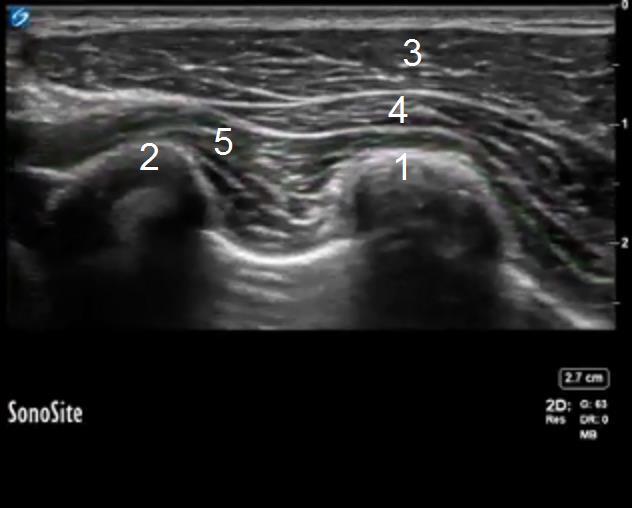

鋸の解剖学 2 イメージ

第3肋骨

第 4 肋骨

大胸筋

Pectoralis Minor Muscle (腱膜)

前鋸筋 (肋骨に接続)